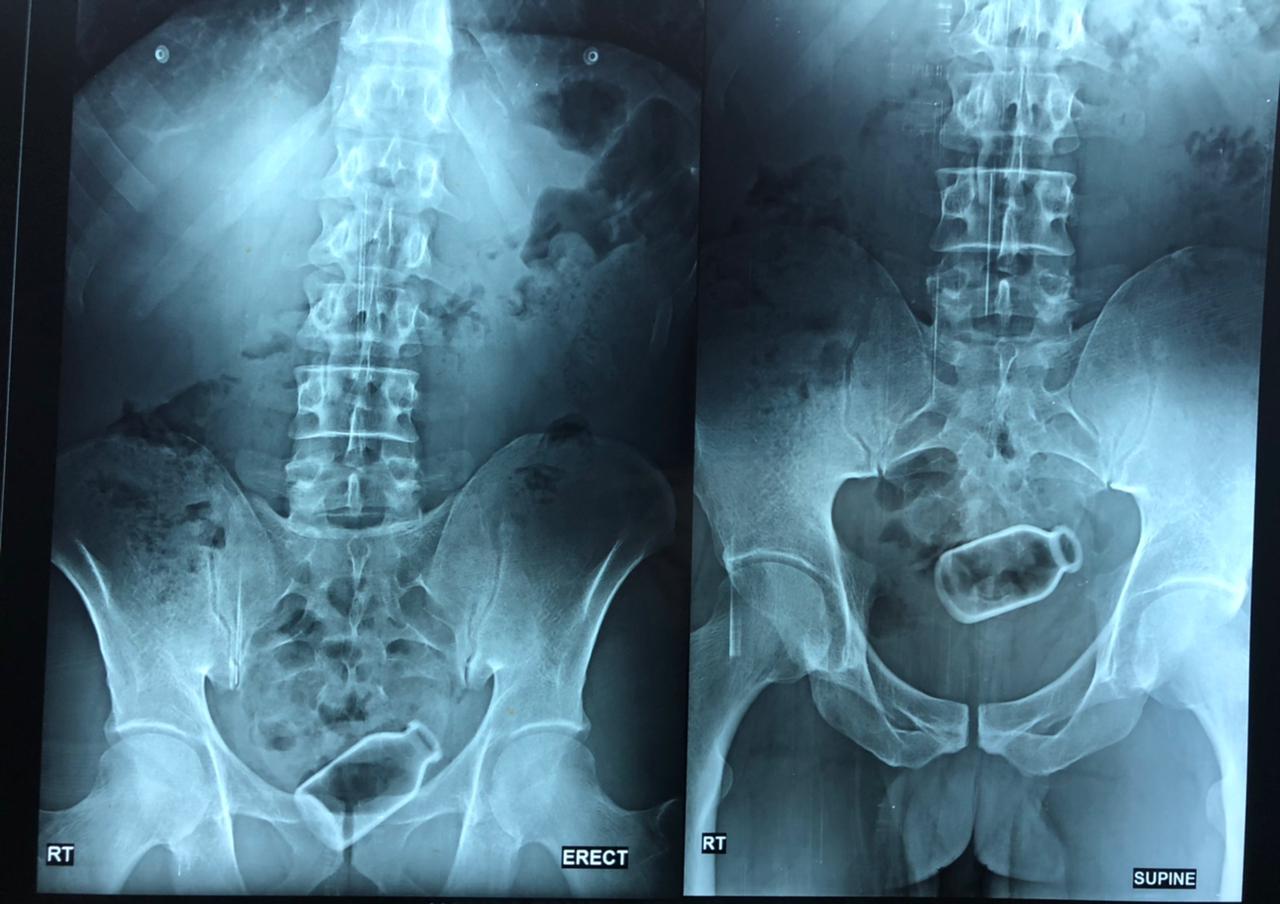

بطول 8 سم، استخراج زجاجة من قولون مريض بمستشفى جامعة المنصورة

نجح فريق طبي بمستشفى المنصورة التخصصي وتحديدا داخل قسم جراحة المناظير في استخراج زجاجة من قولون مريض باستخدام المنظار الطبي بدون جراحة.

جراحة المنظار تمت للمريض "حمادة ا " 38 سنة يعاني من أمراض نفسيه، حيث قام الفريق باستخراج زجاجة طولها ٨ سم من قولون المريض بدون جراحة.

وأكدت الدكتورة أسماء أن إحراء المنظار للمريض استغرق قرابة الساعة، وأوضحت أن المريض أدخل الزجاجه عن طريق فتحة الشرج ووصلت للقولون منذ أسبوعين